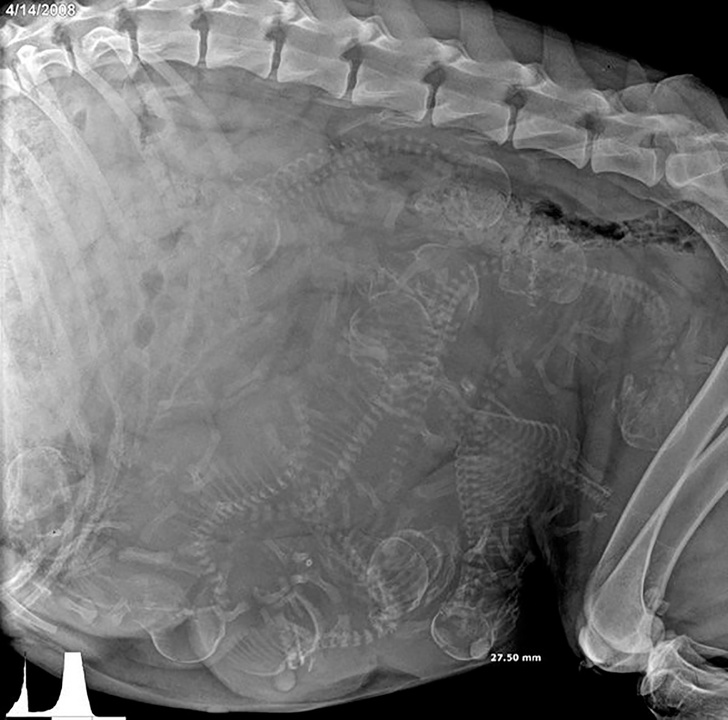

3.怀孕的狗的X光片

©GoodGriefWhatsNext / Reddit